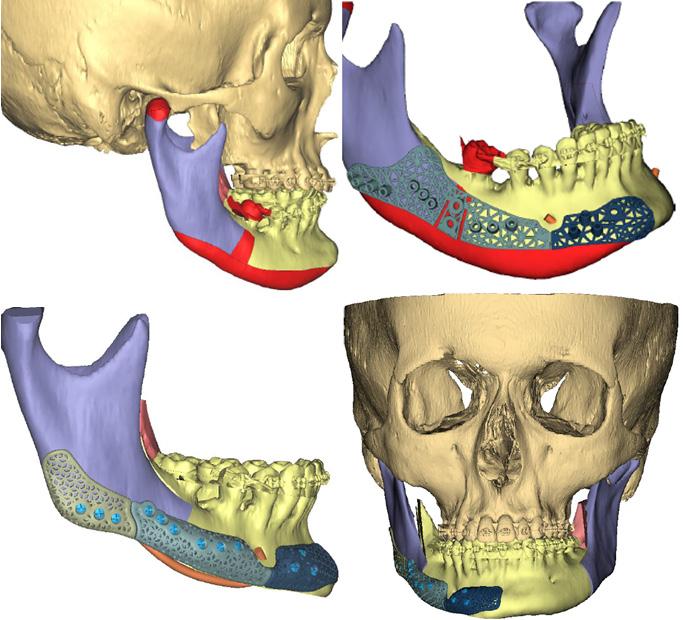

Computer-guided customised treatment of unilateral condylar hyperplasia by proportional condylectomy and orthognathic surgery

Wang D, Smit R, Harrison J and Sealey C

Primary inferior alveolar nerve protection: a CAD/CAM approach

Betar N, Badri D, McCombe A and Finn B